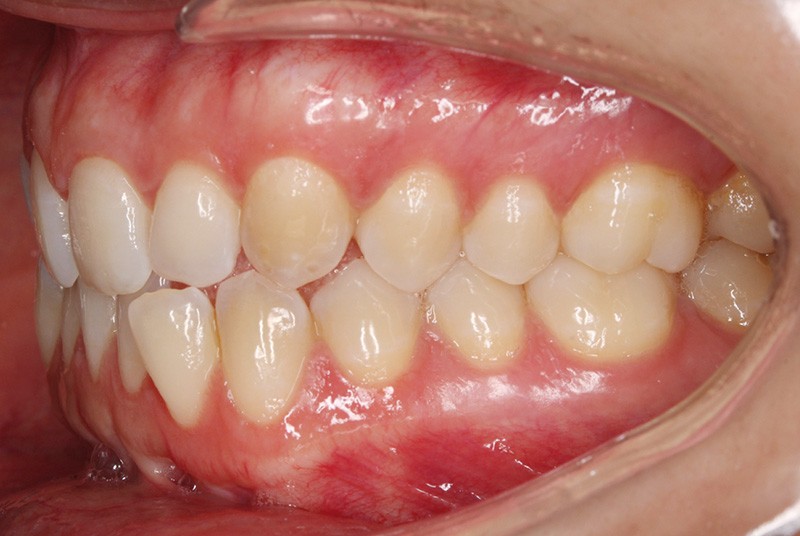

Elle présente une classe I dentaire en denture adulte. Son sourire est perturbé, notamment par la microdontie de son incisive latérale maxillaire droite (la 12). On constate un encombrement modéré au maxillaire (bimarginotopie mésio-palatine et disto-vestibulaire de 13) et plus marqué à la mandibule (monomarginotopie mésio-vestibulaire de 32 et de 43) (fig. 1-6).

Les milieux inter-incisifs ne sont pas coordonnés, à torts partagés, avec une légère déviation à droite du milieu inter-incisif maxillaire et une déviation plus marquée à gauche du milieu inter-incisif mandibulaire ainsi que du point menton. 32 et 33 présentent une tendance à l’exoclusion.

Le plan de traitement a pour but d’augmenter l’espace disponible pour la restauration coronaire de 12, afin de restaurer l’esthétique du sourire, d’aligner les dents, de coordonner les milieux inter-incisifs et de modifier les angulations des incisives et des prémolaires, sans modifier les rapports molaires de classe I.